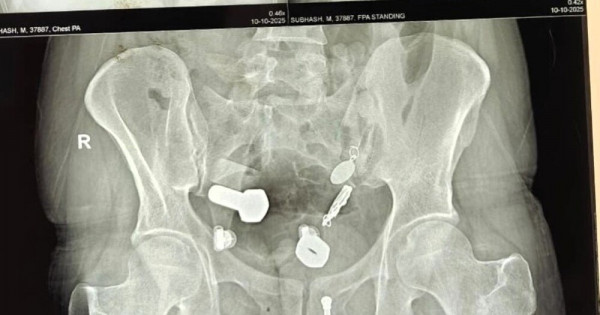

Родственники привезли 34-летнего мужчину в больницу, когда он почувствовал сильную боль в животе и не мог есть и пить. Сканирование показало, что в его пищеводе застряли часы, а в толстом кишечнике оказались металлические фрагменты, гайки и болты.

Врачи обнаружили целую коллекцию в животе пациента.Хирурги попытались удалить предметы с помощью эндоскопии, но потребовалась полостная операция, она продлилась три часа.

Через небольшой разрез в брюшной полости хирурги извлекли часы и другие инородные тела.Мужчина поступил в больницу Саваи Мансингх в Джайпуре, Индия, 9 октября. Сейчас он восстанавливается.